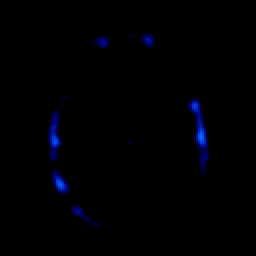

glioma overlay -- Slice #24

[Home][Help][Clinical] Slice 24

Click on sagittal image to select slice. Click on thin tickmark to change timepoint, or thick tickmark for overlay.